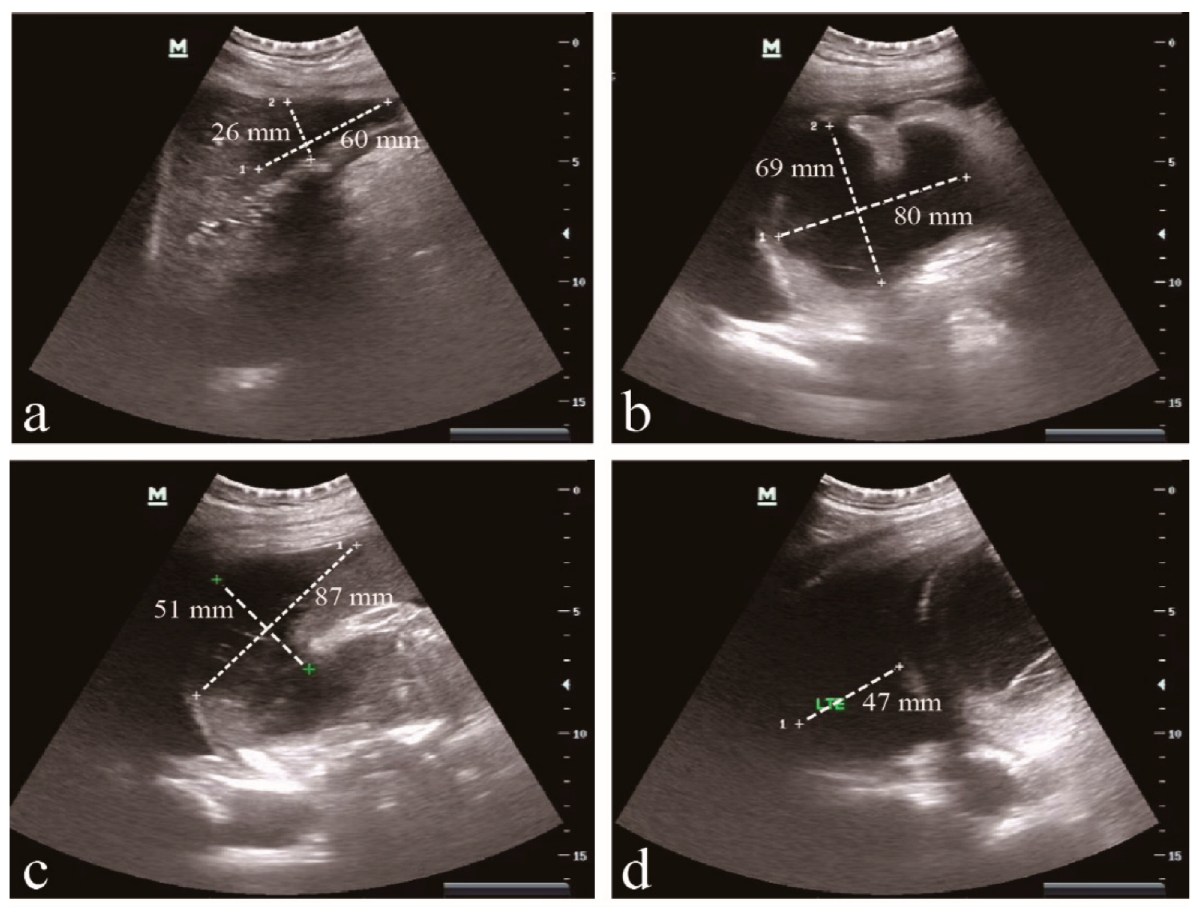

2.1. Patient Information and Clinical Characteristics